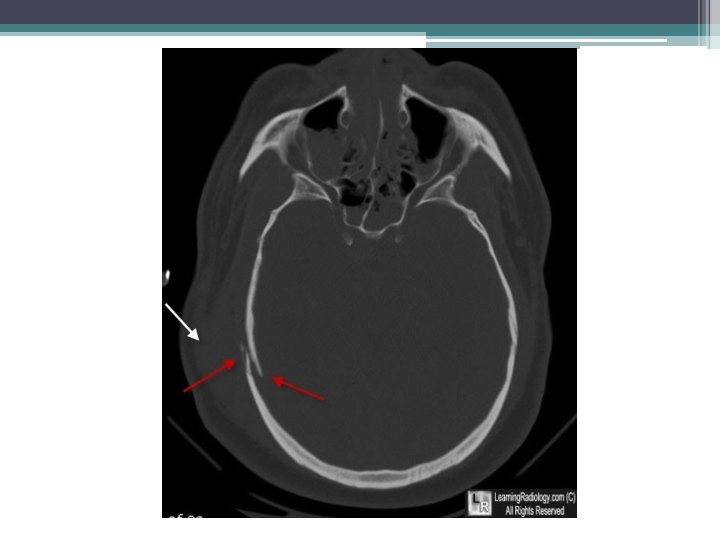

• 7 -Depressed Fracture: occurs in the skull, usually resulting from blunt force trauma.